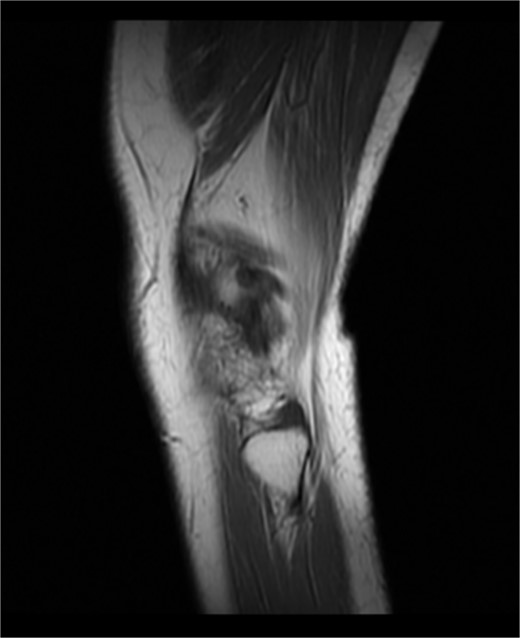

Preoperative physical examination of this patient demonstrated varus deformity of right knee joint for 20° and localized swelling. Besides, the patient’s temperature was 36.5°C, while there was obvious tenderness around her right knee joint, with ROMO ° of −70°. In addition, all of the detection results including internal and lateral square stress test, drawer test and floating patellar test of this patient were negative, whereas the patella milling test was positive. The right lower extremity ends feel and muscle tone in the right lower limb of the patient was normal. Additionally, MRI scan of the right knee joint of this patient unveiled the following results: (i) the bone marrow of the patient’s right leg was swollen; (ii) the right knee medial meniscus anteriorposterior Angle II° got loss, and lateral meniscus anterioranterior Angle III° was injured; (iii) the patient suffered injuries on the anterior cruciate ligament, posterior cruciate ligament and fibular collateral ligament of the right knee; (iv) a small amount of fluid was accumulated in the right knee cavity and suprapatellar bursae (see Fig. 1). Moreover, the front and lateral chest radiographs of the patient revealed no obvious abnormalities in both lungs and thoracic vertebra degeneration. No obvious abnormality was found in both lower limb arteries and bilateral deep veins of lower limbs, and both great and small saphenous veins blood circulation was flow smoothly. Preoperative laboratory assessment results of this patient were as follows: The white blood cells (WBC) count was 6.98 × 109/L (The proportion of neutrophils was 63.70%), the concentration of interleukin-6 was 7.60 pg/ml and the erythrocyte sedimentation rate was 22 mm/h.

Pre-operation MRI image of the right knee joint of this patient.